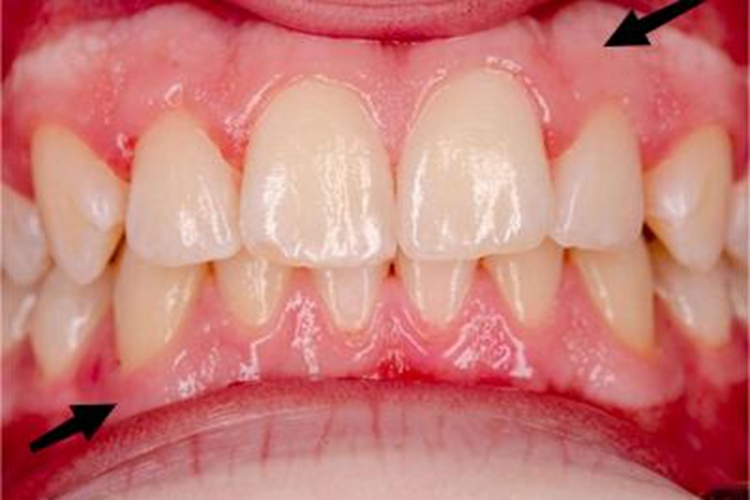

局限型侵袭性牙周炎患者受累部位黏膜可出现肿胀,进而颜色变浅,外观似白斑,皮损形状不规则,部分边缘发红,触摸时有轻微的不适感。